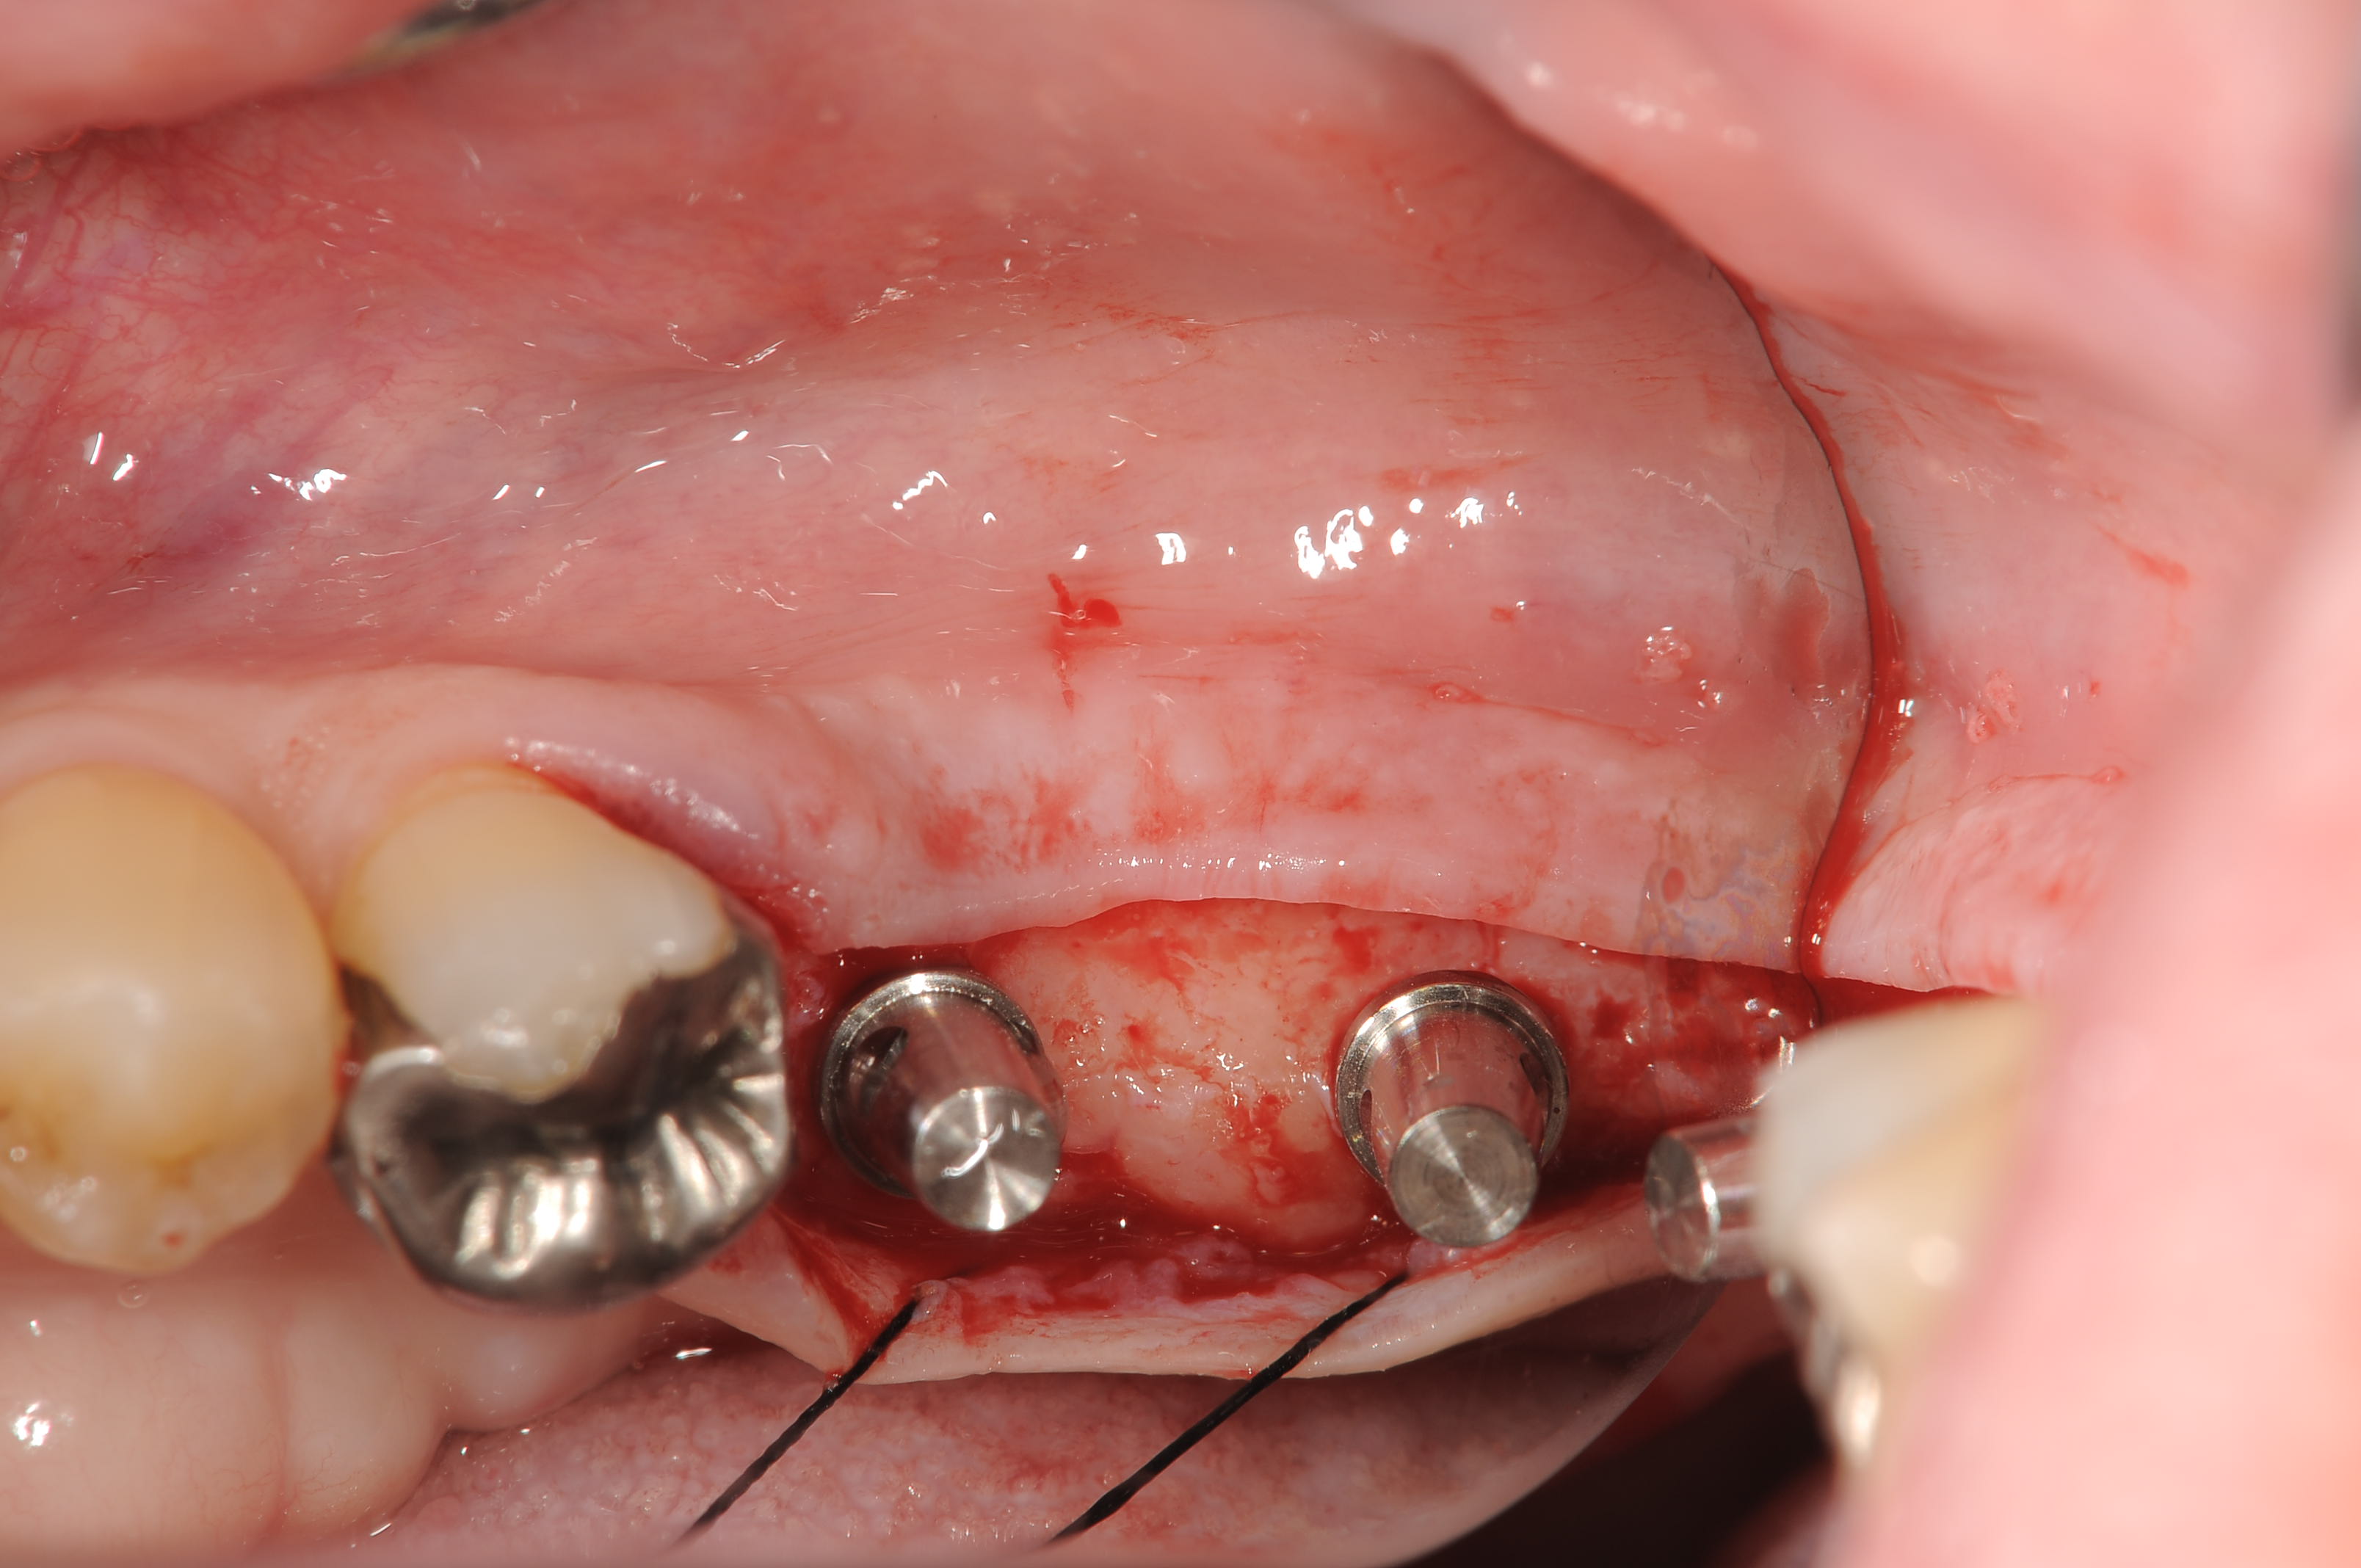

埋入部位の骨、角化歯肉の量も十分でしたので、サイブロンプロEXのワイドボディー11mmと9mmを2本埋入しました。

歯槽粘膜の厚みが薄かったので、埋入深度を0.5mm程度骨縁下に設定し、1mmカフのプラットフォームシフトアバットメントを使用しセメント合着の上部構造を制作予定です。

埋入部位の歯槽骨は良好ですが、粘膜がやや薄いタイプです。

0.5mmのエクスターナルベベルが骨縁下に入るように埋入しました。